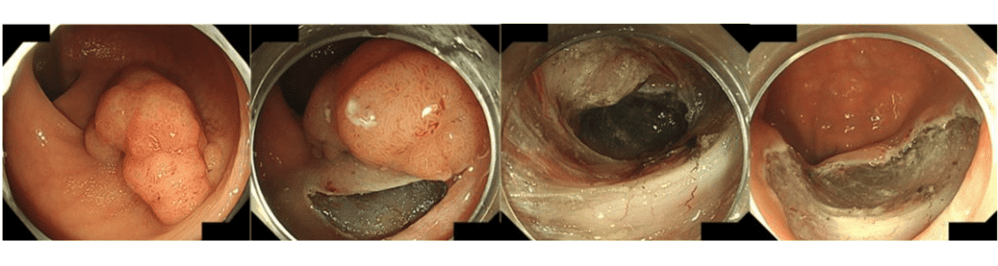

当院では、大腸がんや腺腫(ポリープ)に対する内視鏡による切除治療を、年間約1,500件行っています。内視鏡で切除できる大腸がんには、以下のような方法で対応しています。

- 内視鏡的粘膜下層剥離術(ESD)

がんが大腸の粘膜の深い部分まで入り込んでいる場合は、リンパ節や他の臓器に広がっている可能性があるため、内視鏡での切除はできません。ただし、一括で切除できる大きさで、がんの広がりが粘膜内および粘膜下層の深さ1mm(1000μm)以内であれば、ESDなどの方法で積極的に内視鏡治療を行っています。

内視鏡治療を行うことにより、大腸切除による腸管の機能障害や手術による体への負担、長期の入院を回避し、治療前とほぼ同様の生活を送ることが可能となります。

代表的な内視鏡治療方法

内視鏡的切除術の適応となる大腸のがん・腺腫に対する内視鏡切除方法は病変の形態や大きさによって使い分けています。代表的な方法は下記のとおりです。

粘膜の下に針で薬液を注入し、スネアを使用し熱を加えて切除する方法です。ある程度の大きさ(20mm程度まで)の茎のない病変に対して用いられます。 - 内視鏡的粘膜下層剥離術(ESD)

粘膜の下に薬液を注入し、電気メスで病変の周囲の粘膜を切開し、病変を少しずつ剥離して切除する方法です。大きな病変や、薬液で病変が持ち上がらないときなどに行います。